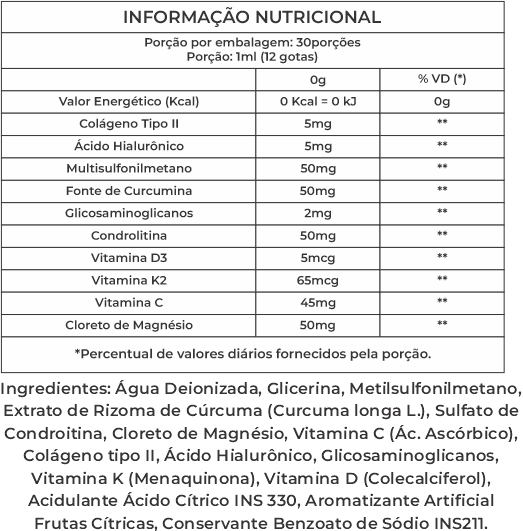

Cúrcuma BCM-95

A cúrcuma é contém propriedades anti-inflamatórias naturais que combate a inflamação articulares como osteoartrite, artrite reumatoide, artrose e outras doenças das juntas.

Colágeno Tipo II

Ele atua na reposição e recuperação de movimentos, da cartilagens e melhora a saúde das juntas.

Ácido Hialurônico

O ácido hialurônico analgésico muito utilizado para tratamento das dores.

Magnésio

O magnésio, além de ajudar na diminuição das dores da artrose, osteoartrite melhora na função articular diminuindo a progressão da inflamação.

MSM

É um suplemento de inúmeros benefícios, dentre eles ação antiinflamatória que auxilia nas dores e inchaços articulares

Vitamina K2

A vitamina K2 desempenha um importante papel na prevenção e tratamento da osteoporose, além disso, a Vitamina K2 também pode inibir os depósitos de cálcio nas artérias, prevenindo doenças cardiovasculares.

Tudo o que você precisará fazer é tomar Bio Cúrcuma 1x ao dia. Sendo 12 gotas pela manhã , esta formula e ultra concentrada!.